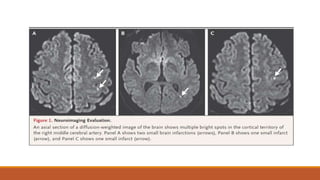

Neuroimaging

• Immediate diffusion-weighted imaging assessed with magnetic resonance imaging (MRI)

is the current preferred test for patients with a suspected TIA since its sensitivity in

detecting brain ischemia is much higher than that with computed tomography (CT)

• In up to 50% of patients with suspected TIA, a bright spot on diffusion-weighted imaging

indicates ischemia.

•Although CT of the head generally cannot be used to diagnose ischemia, when diffusion-

weighted imaging is not available, CT should be performed to rule out another cause of the

symptoms

•A systematic review found that DWI detects corresponding appropriate ischemic lesions

in 16 to 67 percent of patients with classically defined (time-based) TIA.